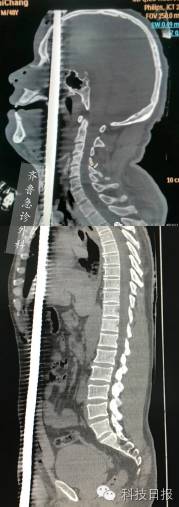

↑伤者钢筋贯穿伤合成图片

6月14日下午3点多,济南某工地,一名46岁的中年男子从5米高空坠落,一支竖起的钢筋从男子的阴部插入,穿透身体从头顶穿出。CT检查结果显示,粗约1.5厘米的钢筋已穿过男子的泌尿、腹部、胸部、口腔、鼻腔、脑部等具体部位。